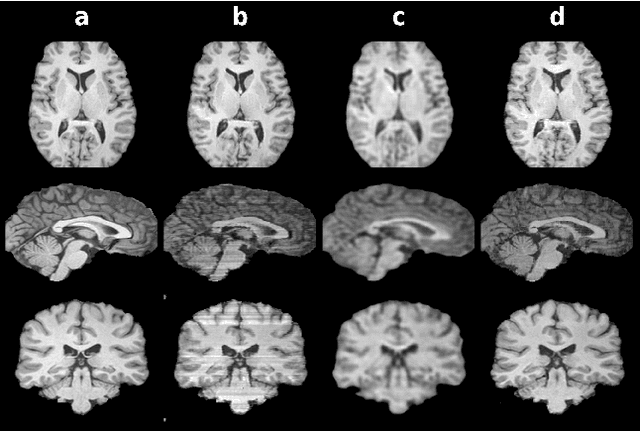

Abstract:Mainstream deep models for three-dimensional MRI synthesis are either cross-sectional or volumetric depending on the input. Cross-sectional models can decrease the model complexity, but they may lead to discontinuity artifacts. On the other hand, volumetric models can alleviate the discontinuity artifacts, but they might suffer from loss of spatial resolution due to increased model complexity coupled with scarce training data. To mitigate the limitations of both approaches, we propose a novel model that progressively recovers the target volume via simpler synthesis tasks across individual orientations.

Abstract:Magnetic resonance imaging (MRI) offers the flexibility to image a given anatomic volume under a multitude of tissue contrasts. Yet, scan time considerations put stringent limits on the quality and diversity of MRI data. The gold-standard approach to alleviate this limitation is to recover high-quality images from data undersampled across various dimensions such as the Fourier domain or contrast sets. A central divide among recovery methods is whether the anatomy is processed per volume or per cross-section. Volumetric models offer enhanced capture of global contextual information, but they can suffer from suboptimal learning due to elevated model complexity. Cross-sectional models with lower complexity offer improved learning behavior, yet they ignore contextual information across the longitudinal dimension of the volume. Here, we introduce a novel data-efficient progressively volumetrized generative model (ProvoGAN) that decomposes complex volumetric image recovery tasks into a series of simpler cross-sectional tasks across individual rectilinear dimensions. ProvoGAN effectively captures global context and recovers fine-structural details across all dimensions, while maintaining low model complexity and data-efficiency advantages of cross-sectional models. Comprehensive demonstrations on mainstream MRI reconstruction and synthesis tasks show that ProvoGAN yields superior performance to state-of-the-art volumetric and cross-sectional models.